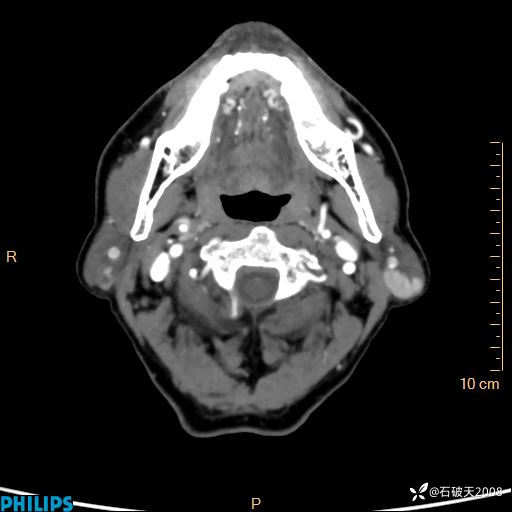

平扫